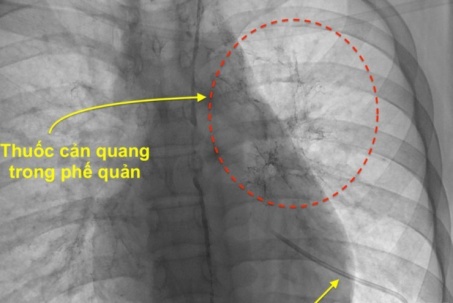

Ho ra máu cảnh giác với sán lá phổi

Sán lá phổi là một bệnh nhiễm trùng do ký sinh trùng sán lá gây ra. Người bệnh mắc bệnh sán lá phổi thường ho ra máu, đau ngực... nếu không được phát hiện và điều trị kịp thời, bệnh có thể dẫn đến viêm phổi, tràn dịch màng phổi...